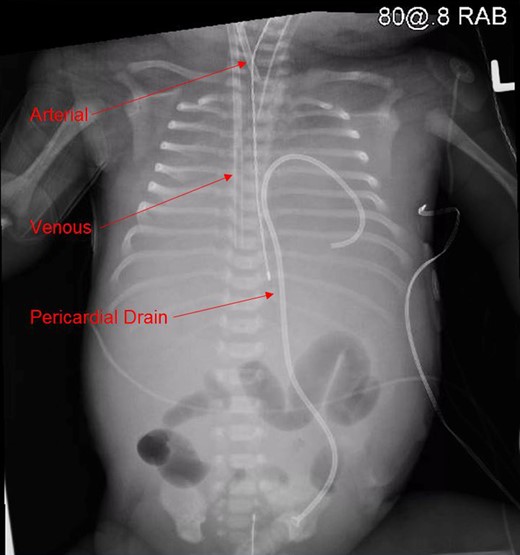

The patient was cooled for 24 h and required hemofiltration through the ECMO circuit for anuria. Approximately 12 h into his ECMO run, the patient developed pericardial tamponade demonstrated on echocardiography, likely secondary to chest compressions, requiring one round of CPR and placement of a percutaneous pericardial drain. Body X-ray (Fig. 1) demonstrated pericardial drain, arterial, and venous cannulae placement. A head ultrasound was obtained the following morning that demonstrated air in the lateral ventricles, Grade I intraventricular hemorrhage and a cerebellar infarct. His neurologic prognosis was deemed by neonatology and pediatric neurology to be exceedingly poor and his mother requested care to be withdrawn. The patient expired within minutes of withdrawal of ECLS. An autopsy was performed that revealed a laceration in the umbilical vein. Autopsy additionally demonstrated myocardial hemorrhage and pulmonary edema consistent with cardiogenic shock.

Body X-ray demonstrating pericardial drain, arterial and venous cannulae placement.